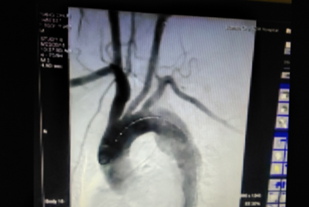

术中(释放支架)

术后(见主动脉血流规则,治疗效果良好)